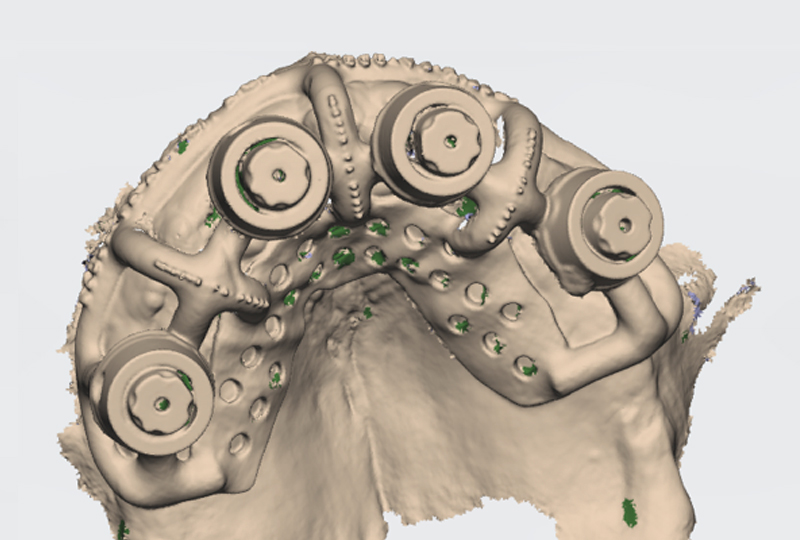

La sistematica IOSFIX® prevede l’utilizzo di un framework metallico (Ringfix®) che unisce gli scan body e assiste, rendendola continua, la scansione dell’arco completo dove dobbiamo realizzare la riabilitazione implantare-protesica: la continuità di scansione riduce gli errori di stitching. Ringfix® presenta dei markers a forma di tronco di cono la cui posizione nella struttura viene misurata con un sistema di misurazione delle coordinate. Questo framework fornisce pertanto informazioni sulla posizione sull’asse X, Y e Z dei markers. Vengono poi usati sistemi di progettazione computer assistiti per calcolare la posizione dell’impianto utilizzando come riferimento la posizione dei markers calibrati. In ultimo la posizione e le misure note sono utilizzate per correggere le discrepanze della scansione intraorale.

A questo punto il flusso di lavoro prevede che la scansione orale con gli scan body sia utilizzata per la costruzione del framework metallico, il Ringfix® (Figura 13), che poi sarà di nuovo scandito nel secondo appuntamento dei tre che sono necessari alla realizzazione di un full-arch a sostegno implantare.

Durante la visita successiva a quella delle impronte (secondo appuntamento) veniva effettuata la prova estetica utilizzando dei prototipi delle protesi definitive. Infatti i progetti venivano stampati in 3D in resina (Dental-try®, Asiga) e provati per verifiche di congruità e approvazione del paziente (Figura 14). In questa stessa fase si validavano le mesh per ottenere delle basi di lavoro virtuali corrette. Il Ringfix® era collocato in bocca e fissato mediante resina fotopolimerizzabile a dei particolari scanbody chiamati Scantransfer (Scantransfer®, IPD) (Figura 15).

Gli Scantransfer prima del loro impiego sono misurati utilizzando un micrometro. L’azienda produttrice dichiara che la loro lunghezza è di 12,500 mm. In realtà dalle misurazioni effettuate si trovano discrepanze fino a +/- 9 micron. Anche queste differenze sull’asse Z sono corrette dall’avanzato algoritmo su cui si basa la sistematica IOSFIX®. L’insieme Ringfix®-Scantransfer® viene scandito di nuovo e analizzato (Figure 16,17).

In primo luogo si accoppiano le matematiche sconosciute dell’area di mesh relativa allo Scantransfer® con le loro corrispondenti matematiche conosciute del software di misurazione. Durante la sovrapposizione si ricerca una sorta di best-fit compensando anche il generale aumento volumetrico che le scansioni subiscono durante la presa delle impronte per i noti fenomeni legati all’illuminazione di oggetti. In tal senso si usano delle matematiche disponibili in diverse compensazioni volumetriche scegliendo quella che meglio si adatterà alla scansione. Essendo il RINGFIX® un sistema calibrato, per comparazione, le dimensioni di qualsiasi componente scandita è conosciuta: questo consente di correggere sia la precisione che la verità dimensionale di qualsiasi sistematica IOS utilizzata. Si effettua poi un confronto tra il centroide dell’impianto-Scantransfer® e quello conosciuto e misurato dei markers a forma di tronco di cono del Ringfix®.

Le differenze rilevate tra questi due vettori nell’asse X-Y, Z e nella loro angolazione servono per la correzione della mesh e soprattutto per il corretto posizionamento della matematica implantare (Figure 18,19). La posizione definita e corretta a questo punto sarà la stessa di quella reale.